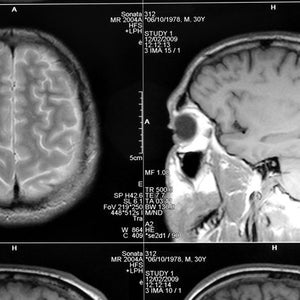

Recipient National Institute of Health announces plans to study sports-related TBIs.